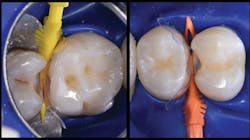

Two key components for tight contacts are wedges and separators; in the case of the Biofit Posterior Matrix System (Bioclear Matrix), the Diamond Wedge and the Twin Ring Separator are used. It is important to use a wedge with a low profile, which provides a gingival seal without distortion of the matrix. Additionally, the separator should be able to provide strong separation and help to seal the matrix along the gingival line angles.

The final piece of the puzzle is the composite materials. In this case, Filtek One Bulk Fill Restorative (3M) and Filtek Bulk Fill Flowable Restorative (3M) were used. Bulk filling is more time efficient, technically simpler, and creates a monolithic form. Manipulation of composites and layering is known for a higher incidence of voids and defects. This case demonstrates the method of injection molding, which has the ability to create strong, monolithic, void-free, ideally contoured, mirror-finish restorations. Significant time savings occurs with simpler finishing requirements. Excess composite at the mid buccal, lingual, and occlusal areas is quickly reshaped with a disc. The subgingival area is then finished with a finishing strip. Finally, it’s time to finish and polish using a diamond-impregnated rubber polisher.

In the following case study (figures 1–11), the techniques and methods discussed will be demonstrated with the treatment of a quadrant of four posterior restorations. Four interproximal smooth-surface carious lesions are conservatively treated with two nonretentive saucer preparations and two marginal ridge-preserving opportunistic preparations.